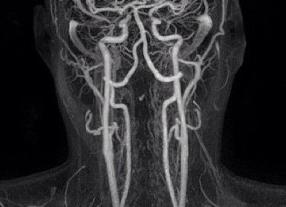

Главными достоинствами магнитного резонанса являются его безвредность и возможность создания трехмерного изображения для выявления всевозможных многочисленных причин синдрома позвоночной артерии. Кроме того, не встает вопрос о том, нужно ли делать МРТ позвоночных артерий с контрастом- при обследовании сосудов позвоночника применение различных режимных протоколов позволяют не использовать дополнительный контраст.

Контрастная МР-ангиография сонных и позвоночных артерий выявляет сужения, сосудистые сгустки (тромбы), расслоения стенки (аневризмы), аномалии строения, являющиеся причиной вертебро-базиллярного синдрома, инсультов.

Показания к МРТ сосудов позвоночника с контрастом:

- Выявление сосудистых разветвлений;

- Оценка проходимости вертебральных артерий;

- Диагностика тромбоэмболии и атеросклероза;

- Определение тактики лечения сосудистой патологии (консервативное, оперативное).